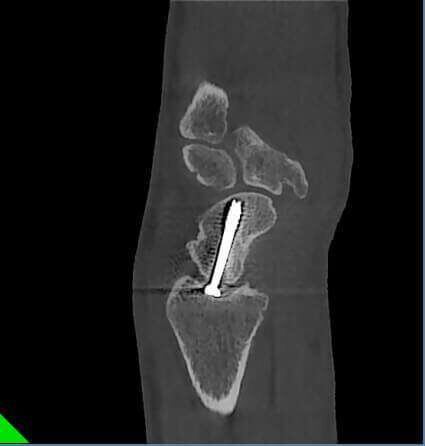

Fractura de escafoides con material de osteosíntesis.